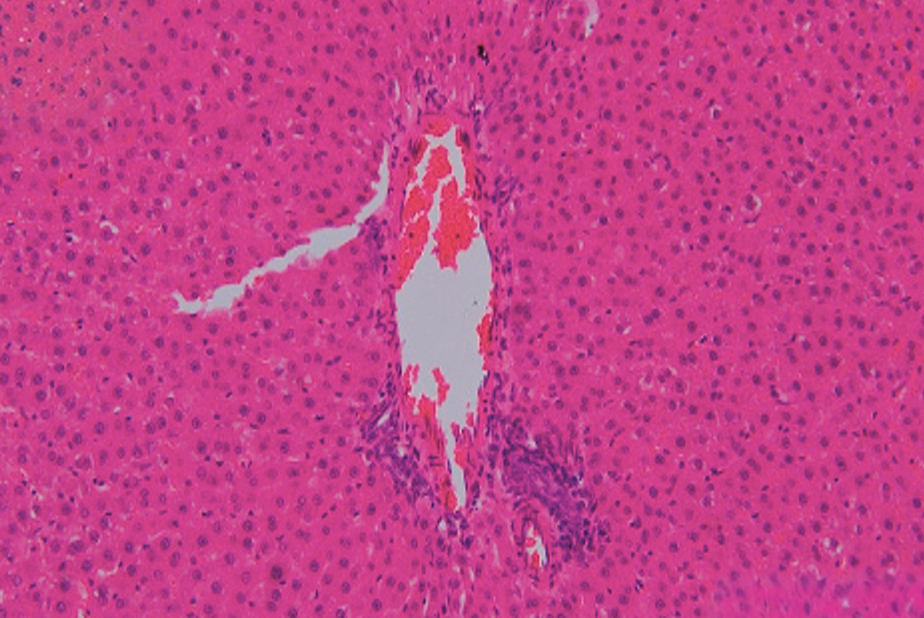

- Esami istopatologici: gli esami del fegato e dei reni hanno mostrato lievi anomalie, come vacuolizzazione e congestione vascolare, che non sono state associate a cambiamenti significativi nei marcatori biochimici.